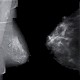

Unter dem Motto „Gegensätze verbinden“ offeriert der Kongress eine Vielzahl verschiedener Themen. Die Schwerpunktthemen auf dem diesjährigen Kongress sind Abdominaldiagnostik, Herz- und Rheumabildgebung sowie Kinderradiologie und Strahlenschutz. Korrespondierend hierzu wird das breite Spektrum der Interventionellen Radiologie diskutiert. Der Kongress und seine Schwerpunkte werden gemeinsam mit den zugehörigen klinischen Fachgesellschaften bestritten. Aber auch „um die Radiologie herum“ behandelt das MTRA-Programm die unterschiedlichsten Themen, z.B. Qualitätsmanagement, technische Neuerungen, Kommunikation und soziale Interaktion. ...